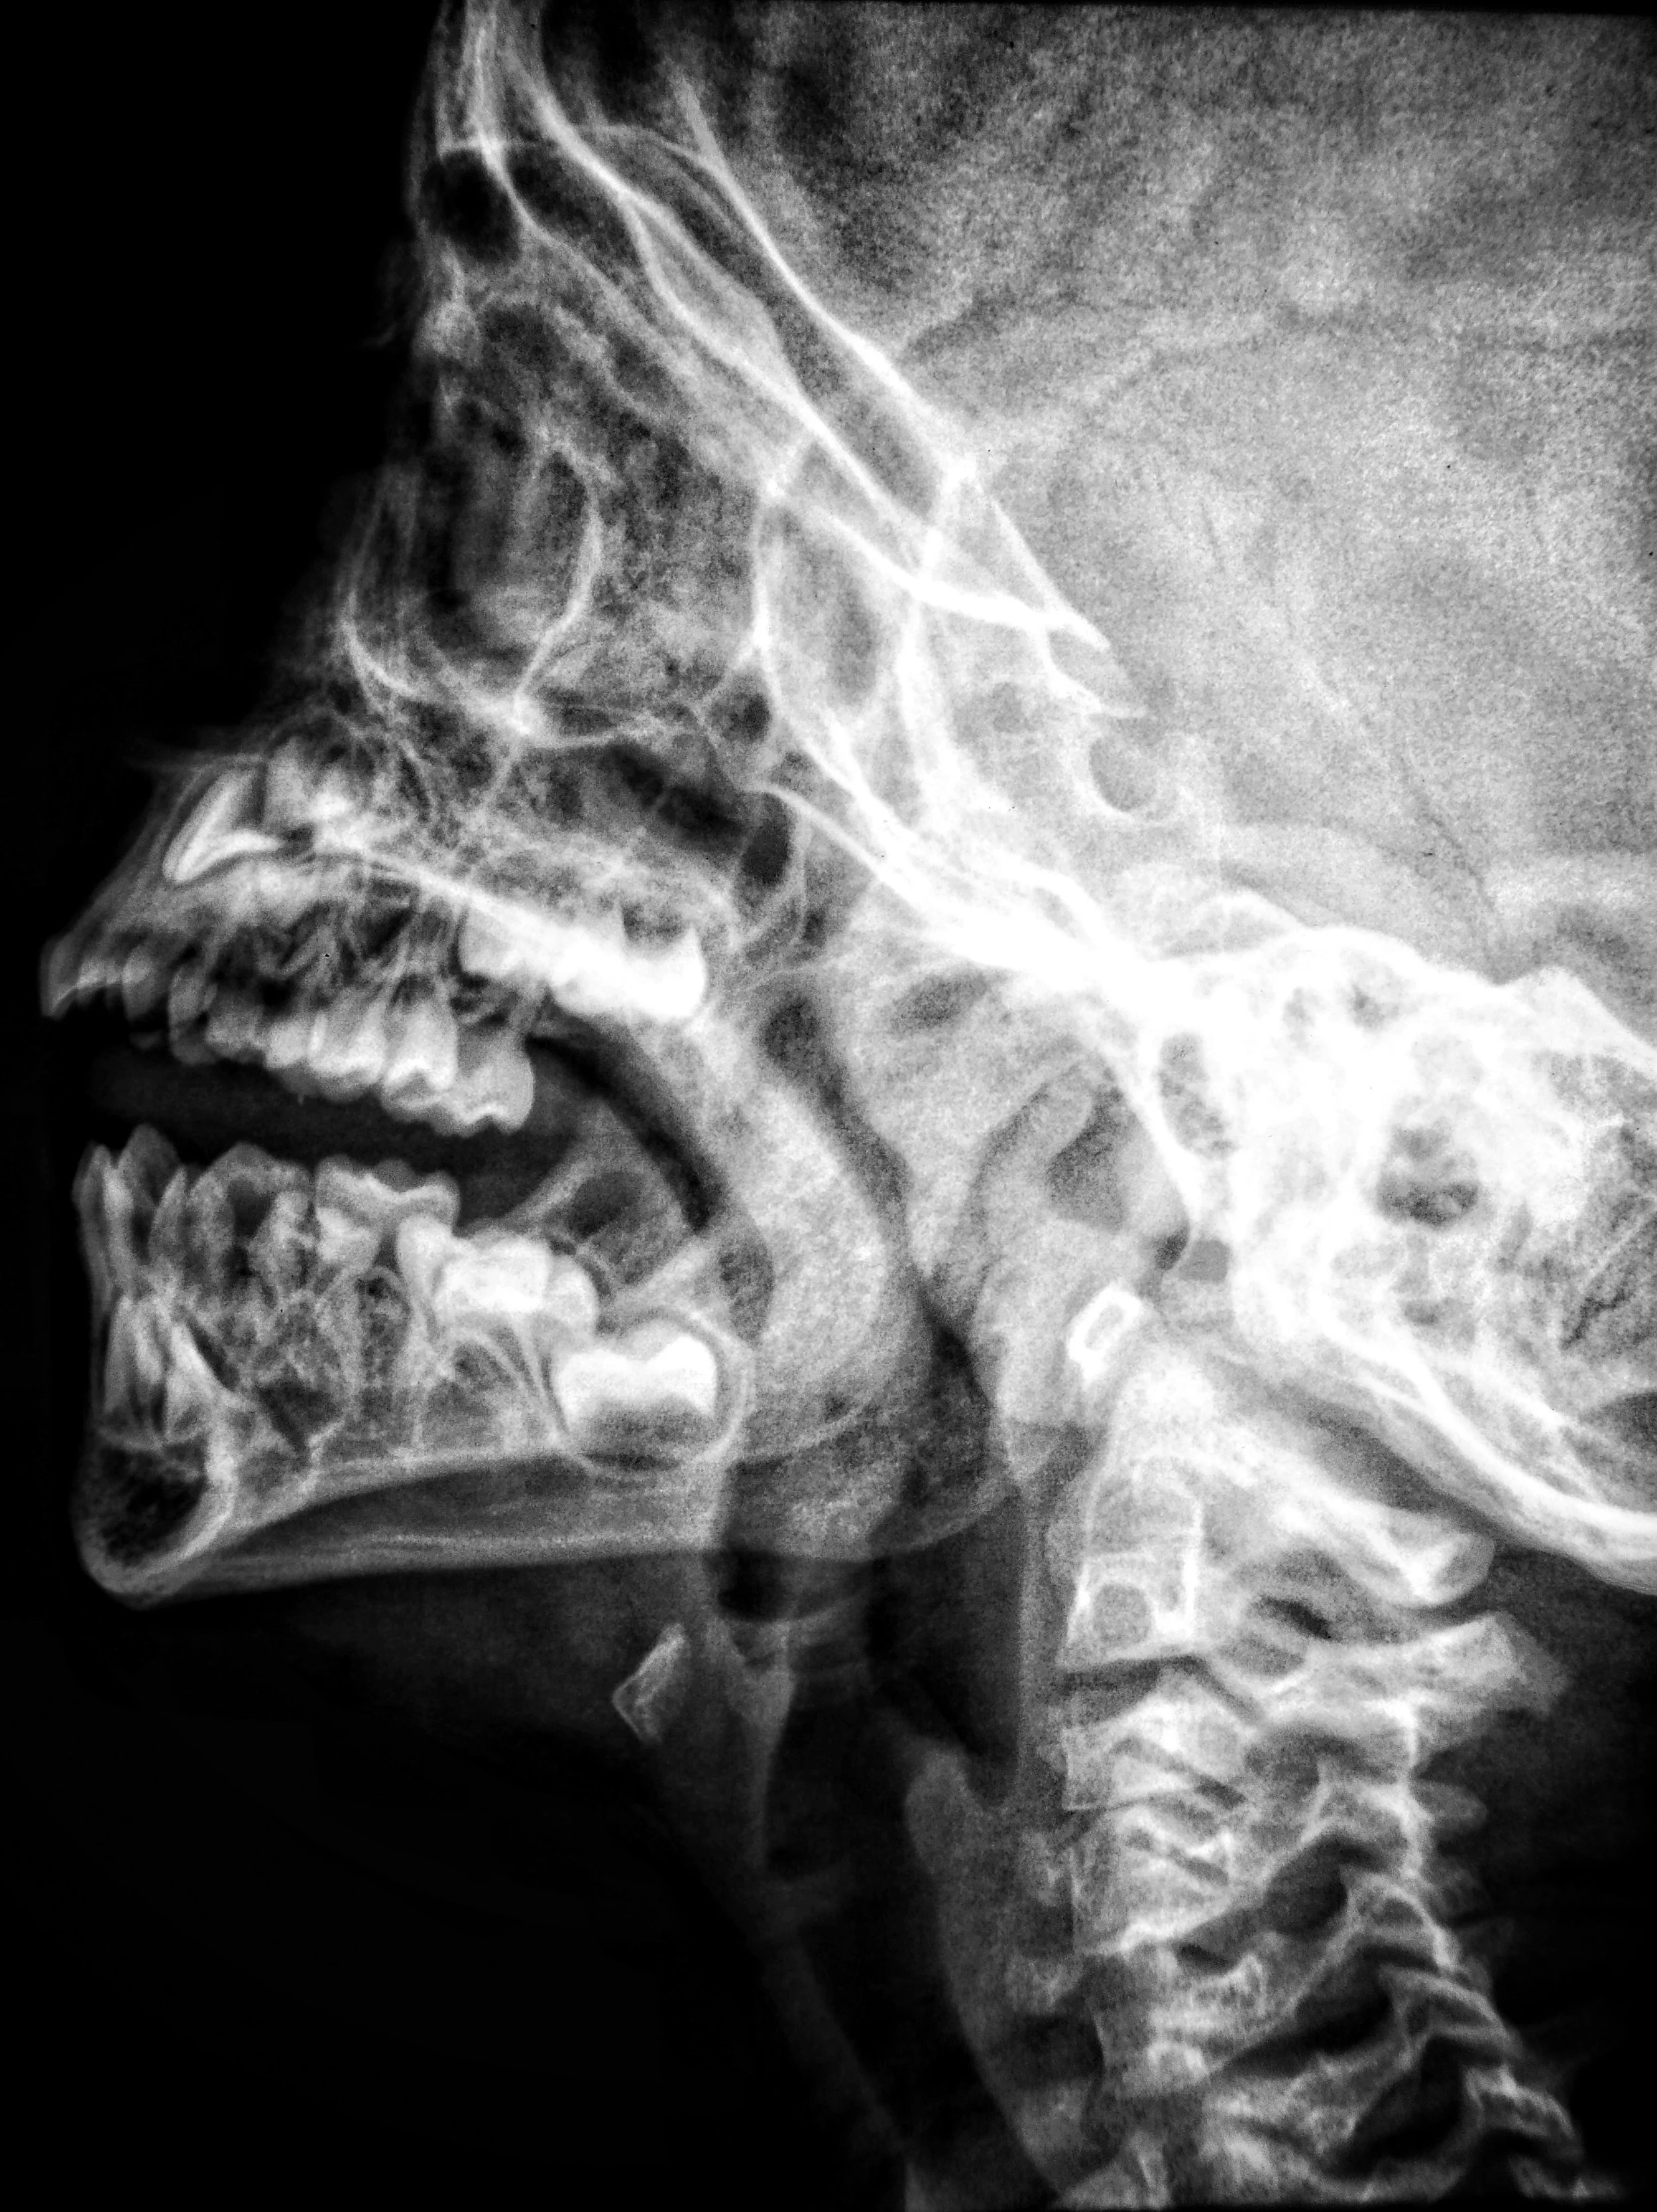

Current research shows a strong anatomical and neurological link between the temporomandibular joint (TMJ) and the cervical spine, meaning dysfunction in one area can directly influence the other. Understanding this relationship is the first step toward long‑lasting relief.

The trigeminal nerve, which supplies sensation to the jaw and face, shares neurological pathways with the upper cervical nerves (C1–C3). This convergence happens in the trigeminocervical nucleus, a region of the brainstem where signals from the jaw and neck overlap.

This mechanism is well‑documented in pain science literature and explains why TMJ disorders often present with neck‑related symptoms.

Forward head posture — common with desk work, phone use, and stress — increases load on the cervical spine and alters jaw mechanics. Studies show that poor cervical posture can change the resting position of the mandible and increase TMJ strain.